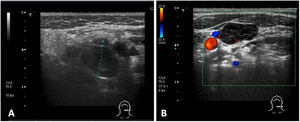

Debido a la persistencia de adenopatías, se solicita una tomografía computarizada (TC) en la que se observan múltiples adenopatías laterocervicales de predominio izquierdo en áreasII, III, IV yV cervicales, de consistencia sólida y de tamaño patológico (fig. 1). Además, se realiza una ecografía cervical para valorar las características de dichas adenopatías, también sugestivas de patología (fig. 2).